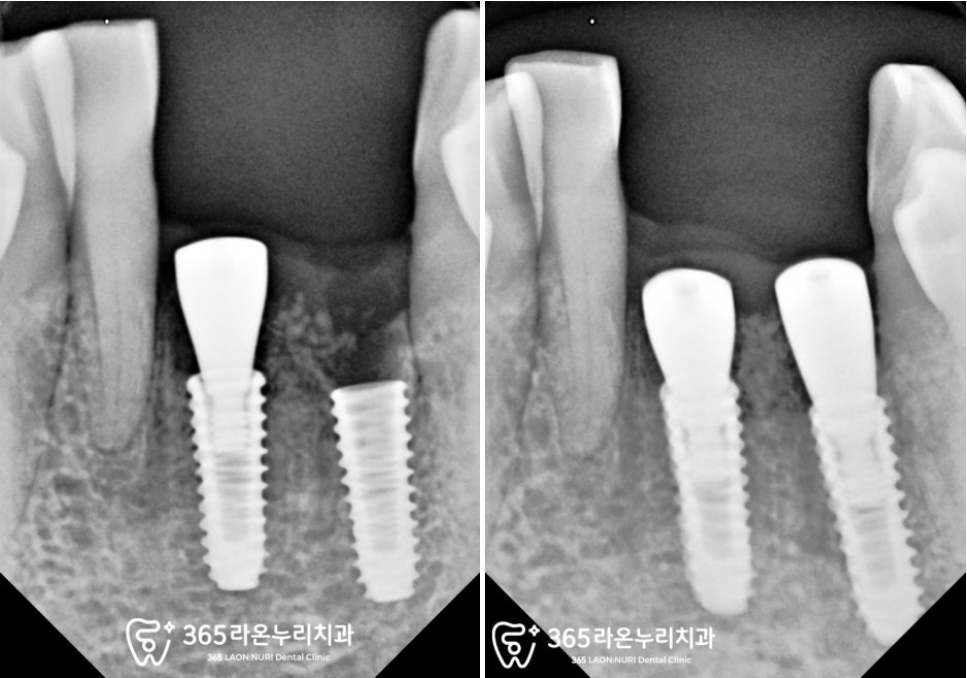

우선 눈에 띄는 아래 앞니부위부터

임플란트 식립을 진행해드렸습니다.

계획된 위치에 잘 심은 모습이

관찰되고 있습니다.

보시는 것과 같이

잇몸뼈가 뿌리 끝까지 녹아

더이상 치아를 지지하지

못하고 흔들리고 있었는데요.